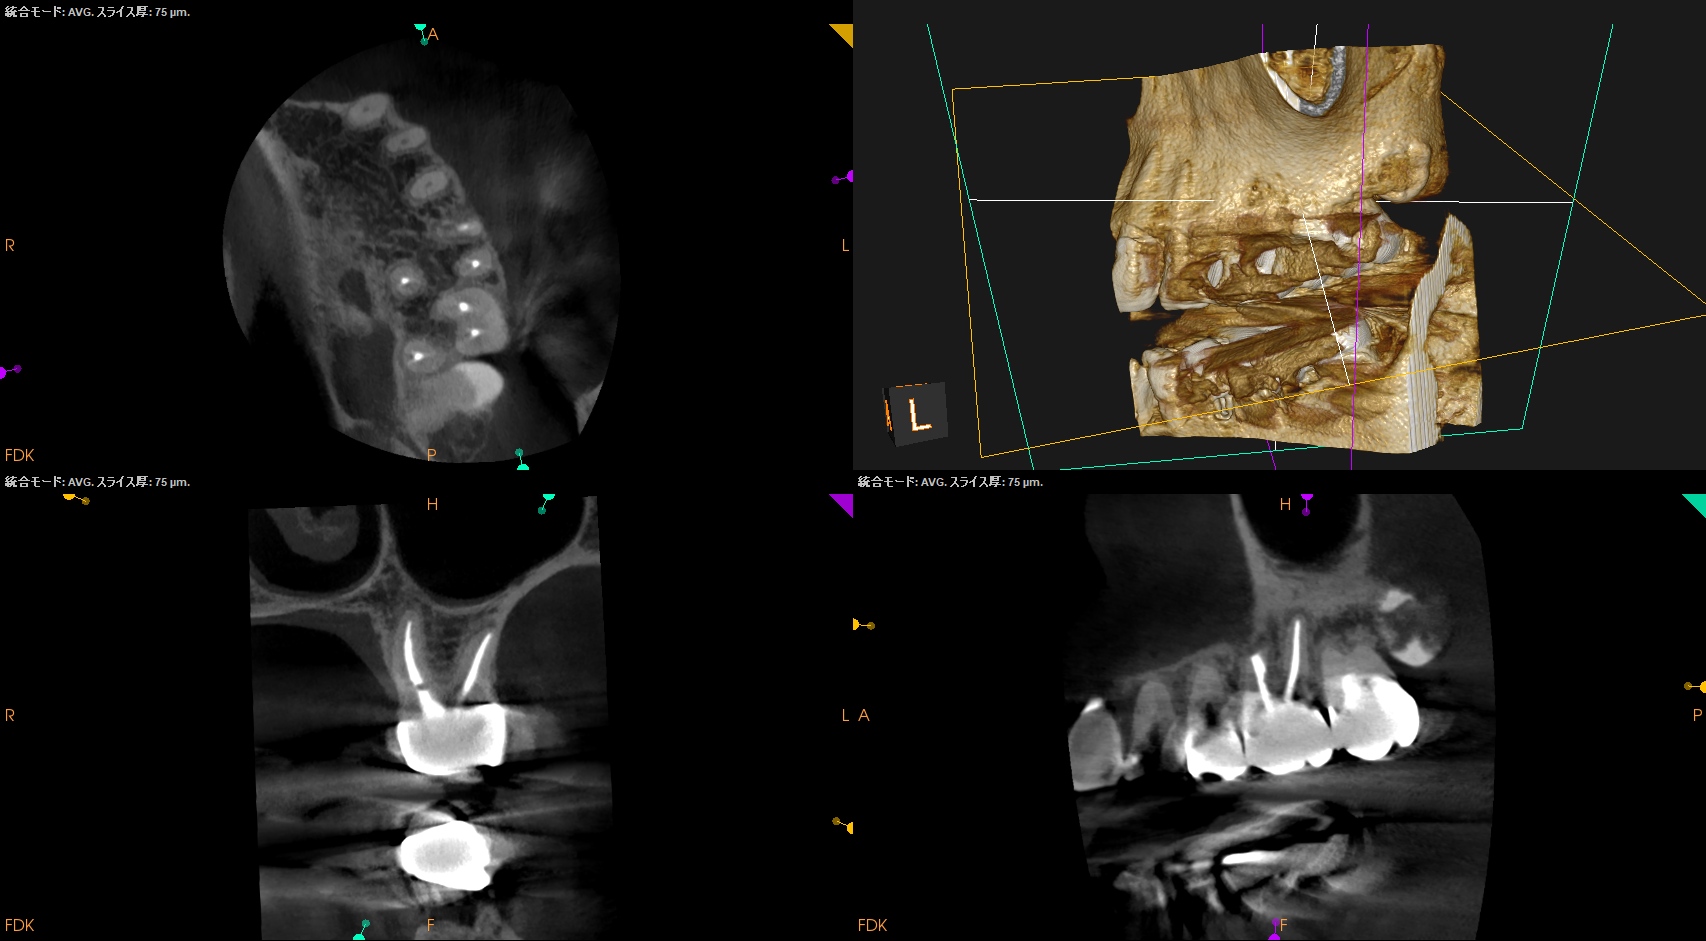

術後にPA, CBCTを撮影した。

#14 Post-op 1yr recall(2026.3.27)

PA, CBCTを撮影した。

外科時と比較した。

問題は劇的に解消した。